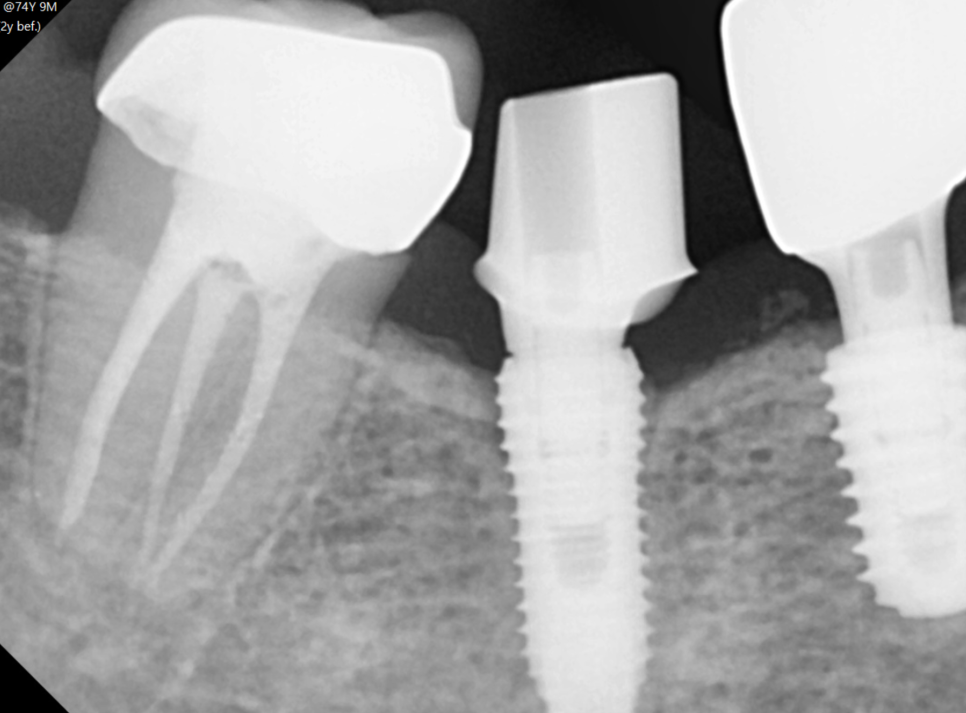

x-ray 분석 등을 통하여 최대한 제품의 정보를 확인하지만

230630

< 임플란트 사후관리 가능한 경우>

-

제품 브랜드를 확인

주변 잇몸 뼈에 문제가 없는 경우

임플란트에 문제가 없는 경우

해당하는 제품을 구해 수리가 가능합니다 .